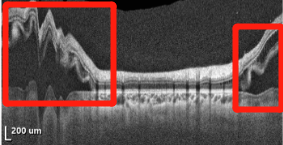

▲小可右眼检查图片

东莞光明眼科医院副院长刘永民解释说,“小可的眼底出现黄斑裂孔,这个裂孔没有及时发现并采取补救措施,才会引发视网膜脱离。”

小女孩叫小可(化名),今年10岁,双眼近视200度,右眼最近三个月突然视力下降,看东西有闪光感,视力仅剩0.05,几乎看不见。到医院经过详细的检查,确诊为黄斑裂孔性视网膜脱离。